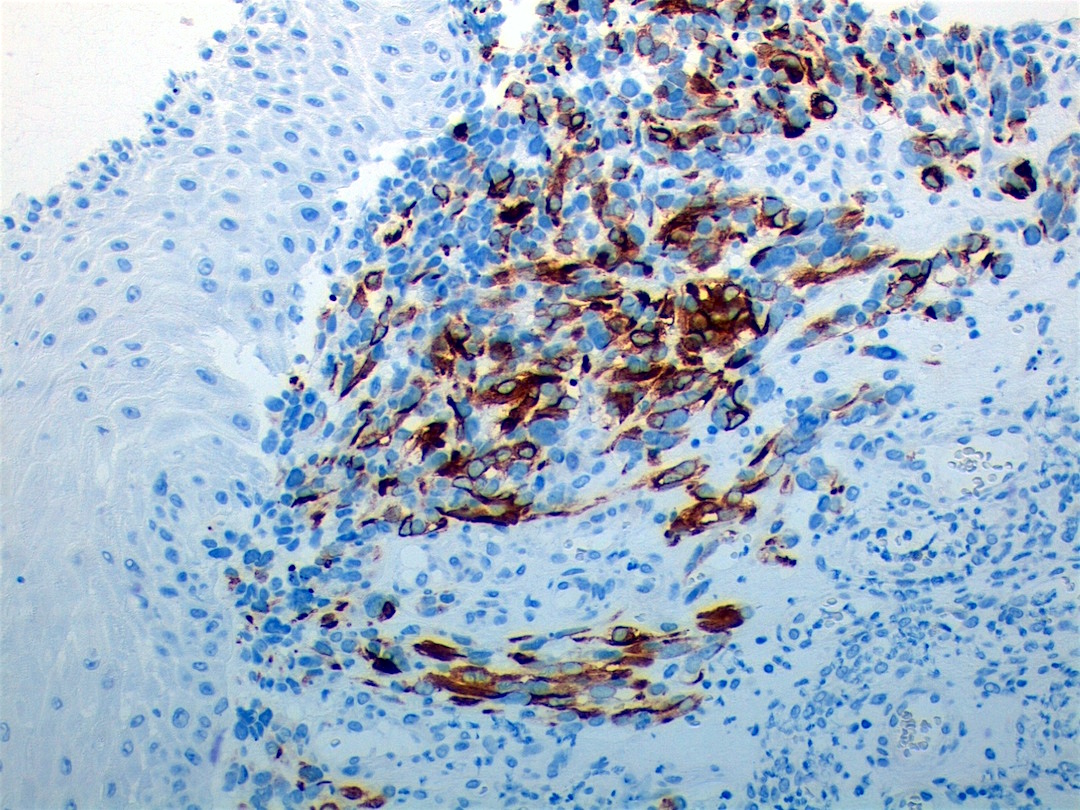

Microscopic (histologic) images

Contributed by Erdener Özer, M.D., Ph.D. and Mark R. Wick, M.D.

Contributed by Carolina Martinez Ciarpaglini, M.D., Ph.D. (Case #276) - tonsillar mass

AFIP images - anaplastic rhabdomyosarcoma

AFIP images - botryoid variant

Positive stains

- Desmin, MyoD1 or myogenin are critical to document (Pathol Oncol Res 2008;14:233)

- Without myogenic differentiation (MyoD1 or myogenin), it is very difficult to diagnose embryonal rhabdomyosarcoma

- These stains will be less diffuse than in alveolar rhabdomyosarcoma and can be extremely focal

- Botryoid variant: Desmin, MyoD1, smooth muscle actin, muscle specific actin (Pediatr Dev Pathol 2005;8:427)